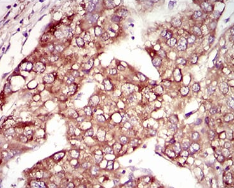

IHC    1/200 - 1/1000